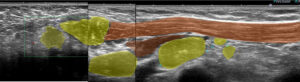

これらエコーをつなぎ合わせたもの

リンパ節は黄色に表現

大胸筋(茶色)の裏に小胸筋(こげ茶色)

大胸筋の外側にリンパ節2つ、大胸筋の裏にリンパ節1個 これら3個がレベルⅠ

小胸筋裏にリンパ節(これが最大で2㎝)これがレベルⅡ

それより内側(奥)に比較的小さいリンパ節2個 これらがレベルⅢ